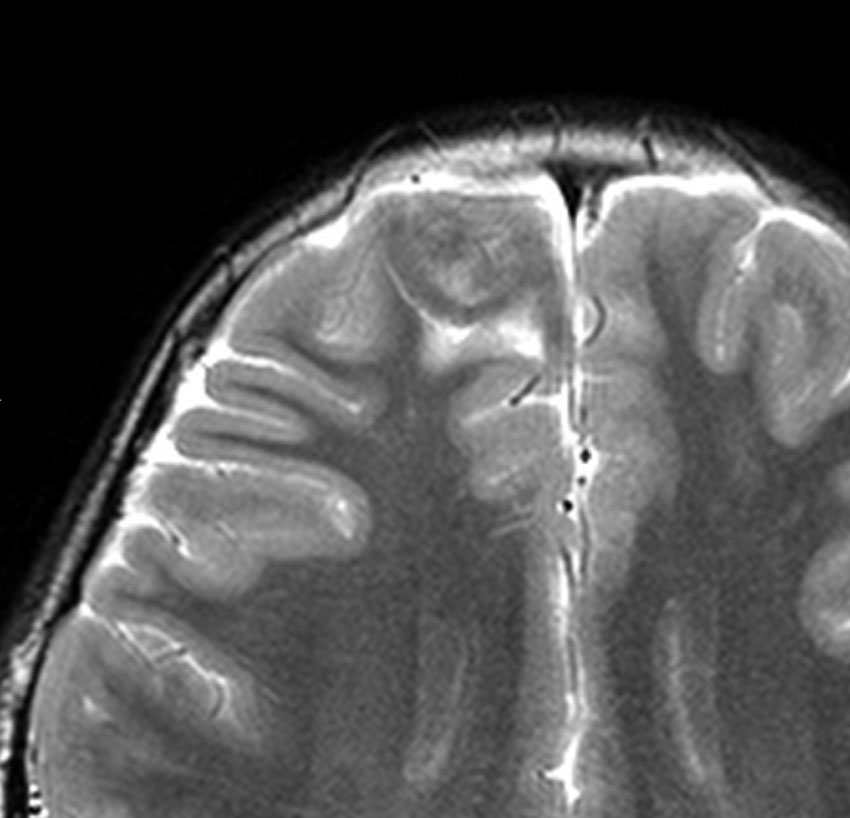

- T2強調画像では低信号領域と血管のflow-voidがみられます

- T2低信号の部分(結節)が強くガドリニウム増強されることも特徴かもしれません

難治性てんかんで発症した小児ですが,どう見てもDNTなのかなと思います。石灰化もありません。一般的に,meningioangiomatosisの術前診断は困難であると言えます。いずれにしても治療はlesionectomyです。

摘出して8年後のMRIです。手術後に発作は完全に消失してmedication freeです。発症後3年で手術摘出したのですが,間に合ったのでしょう。薬物治療を続けて発作期間が長期化してから手術摘出すると単なる病変切除ではてんかんが制御できないことがあります。